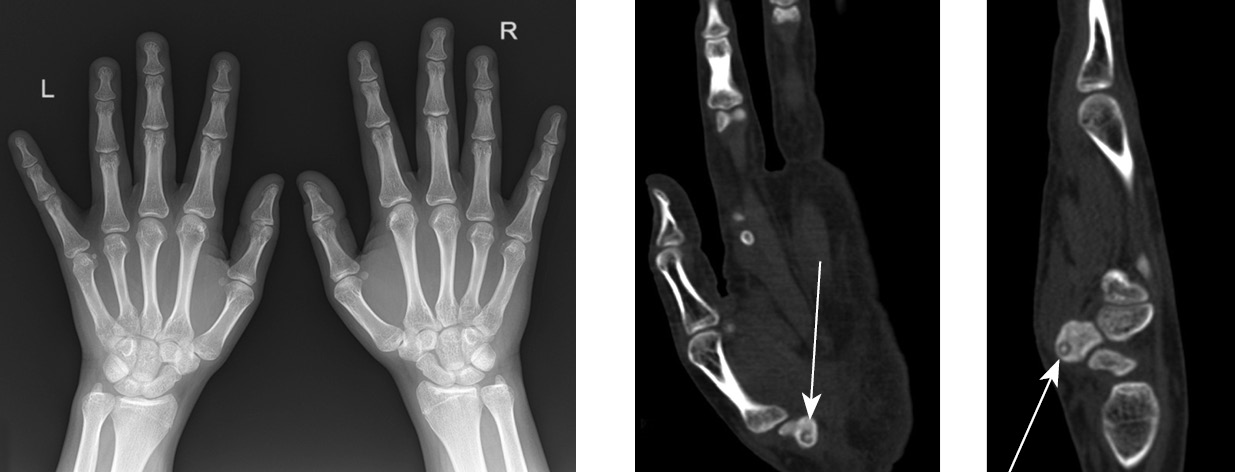

На рентгенограммах кистей в стандартных проекциях — без структурных изменений. При КТ кистей в области бугорка кости-трапеции левой кисти обнаружен отграниченный участок деструкции округлой формы размером 0,41 × 0,47 см со склеротическим ободком по периферии и с центрально расположенным включением костной плотности диаметром 0,2 см. Прилежащие отделы кортикального слоя пораженной кости истончены, периостальная реакция отсутствовала. Анатомические соотношения в лучезапястном суставе, суставах запястья и мелких суставах кисти не нарушены, суставные поверхности четкие, ровные. Костно-травматических изменений не выявлено (рис. 2).

Рис. 2. Пациент П., 17 лет. Рентгенограмма кистей в переднезадней проекции и компьютерная томограмма левой кисти в режиме MPR (фронтальная и сагиттальная плоскости), демонстрирующие локализацию «гнезда» опухоли (указана стрелками)